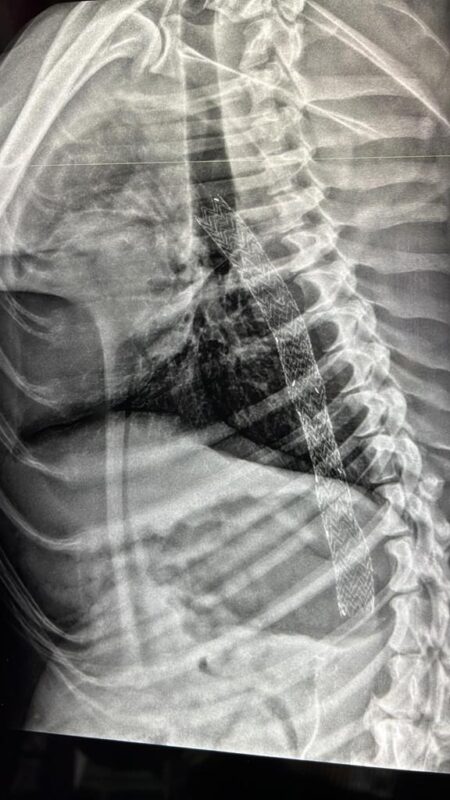

ד"ר ברוכים מספר: "הצוות המקצועי של היחידה לטיפול נמרץ ייצב את מימי ע"י עירויי דם ותרופה לייצוב קרישים, ומימי חיכתה ללא תזוזה לצנתור שיציל את חייה. מפרצת באבי העורקים נחשבת נדירה בכלבים ולרוב נגרמת בשל נדידה של תולעת הפארק שגורמת לחירור ולהיחלשות של דופן אבי העורקים. היות והיא נדירה, ודורשת התערבות מורכבת ומהירה לא נהוג לטפל בכלבים הסובלים ממנה. בהתאם, צנתור באבי העורקים מסוג זה התבצע רק פעם אחת בכלבים , ולכן החלטנו לפנות לתגבורת".

בשבוע שעבר תוך 48 שעות מהגעתה של מימי, הגיע בשעות הצהרים ד"ר גבריאל מהמרכז הרפואי קפלן אל היחידה לטיפול נמרץ וטרינרי בבן שמן, כשהוא מלווה ב ד"ר פבל קלשצ'ב, כירורג לב, המתמחה כעת בכירורגית כלי דם. הציוד לצורך הפעולה נתרם כולו על ידי חברות הציוד הרפואי, לרבות סטנטים מכוסים מיוחדים (חברת NEOPHARM/GORE) והציוד הנלווה (חברות GAD MEDICAL/TERUMO, SHILLO), אלון שחר, נציג חברת NEOPHARM הצטרף אף הוא לפעולה. השלושה פגשו ביחידה לטיפול נמרץ וטרינרי את צוות היחידה, שכלל את ירון, אייל מומחה לכירורגיה וטרינרית, ישי קושניר מומחה להרדמה ויעל גולדמן מתמחה.

הצנתור בוצע בשיתוף פעולה של ד"ר אייל הכירורג הוטרינרי, וצוות כלי דם והוכתר בהצלחה. ד"ר גבריאל: "תיקון מפרצות בצנתור מבוצע בבני אדם כבר שנים רבות. היתרונות כמו גם הסיבוכים האפשריים של פעולות אלה ידועים היטב. תיקון זעיר-פולשני זה החליף כמעט לחלוטין את התיקון בניתוח פתוח שהינו ניתוח גדול, עם סיבוכים רבים והחלמה ארוכה. בניגוד לניתוח בו מוחלף החלק החולה בעורק, בשתל סינטטי, בצנתור מוכנס סטנט מכוסה בד המאפשר זרימת דם דרכו ומונע זרימת דם לשק המפרצת, ובכך מקטין את הסיכון לקרע ומוות מדימום".

הוא מוסיף ואומר לגבי ההבדלים בין בני אדם לבעלי חיים: "החלק הטכני של צנתור בכלב די דומה לצנתור בבני אדם, ולא הייתה צפויה בעיה בתחום הזה. לעומת זאת, היות וכמעט לא בוצעו פעולות כאלה בעבר, לא ניתן היה לצפות כיצד יגיבו כלי הדם של מימי למניפולציות הדרושות לפתיחת הסטנט באבי העורקים".